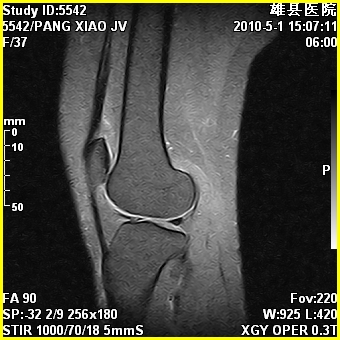

标题: MRI2894:患者右膝关节疼痛两月余,无明显外伤史 [打印本页]

标题: MRI2894:患者右膝关节疼痛两月余,无明显外伤史

右股骨下端前内侧类圆形异常信号,位于干骺端,呈长t1长t2改变,但信号不均,t1图上病灶中心见小片状稍高信号影,t2图上见散在稍低信号影,stir像呈高信号,因病灶较小,缺乏特征性改变,结合患者年龄及部位,考虑嗜酸性肉芽肿可能性大。胫骨关节面下的小囊状异常信号,如果一元论考虑则为嗜酸性肉芽肿,不过发生在这个部位的少见,二元论考虑为邻关节骨囊肿。半月板与前后交叉韧带均未见异常。

右股骨下端前内侧干骺端囊性良性病变,考虑 1内生软骨瘤 2骨囊肿 3肉芽肿。